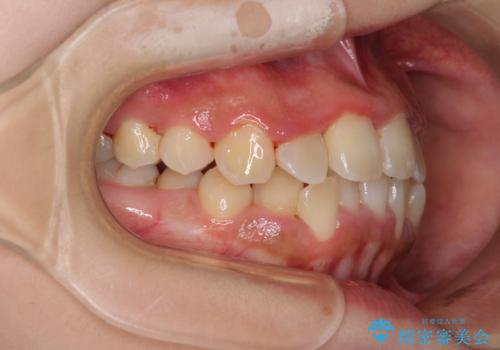

前後に重なった前歯 ワイヤー装置と急速拡大装置を併用したインビザライン矯正

- 前歯の著しい叢生とクロスバイトを気にして来院された患者様です。

叢生が強いため、一見すると抜歯矯正と判断したくなりますが、下顎臼歯が舌側に倒れていることから、上顎骨を側方拡大し、非抜歯矯正の可能性を検討することとしました。

非抜歯矯正が可能となった場合には、インビザラインにて矯正治療を行うこととしました。

急速拡大装置による上顎骨の側方拡大が思った以上にうまくいき、非抜歯での矯正が可能となりました。

内側に倒れていた下顎の臼歯は起き上がり、清掃性も大幅に改善されました。